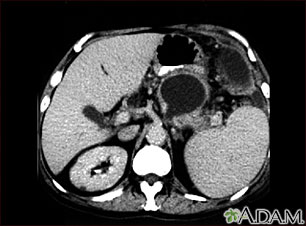

Esta TC del abdomen superior muestra un seudoquiste en el cuerpo o cola del páncreas.